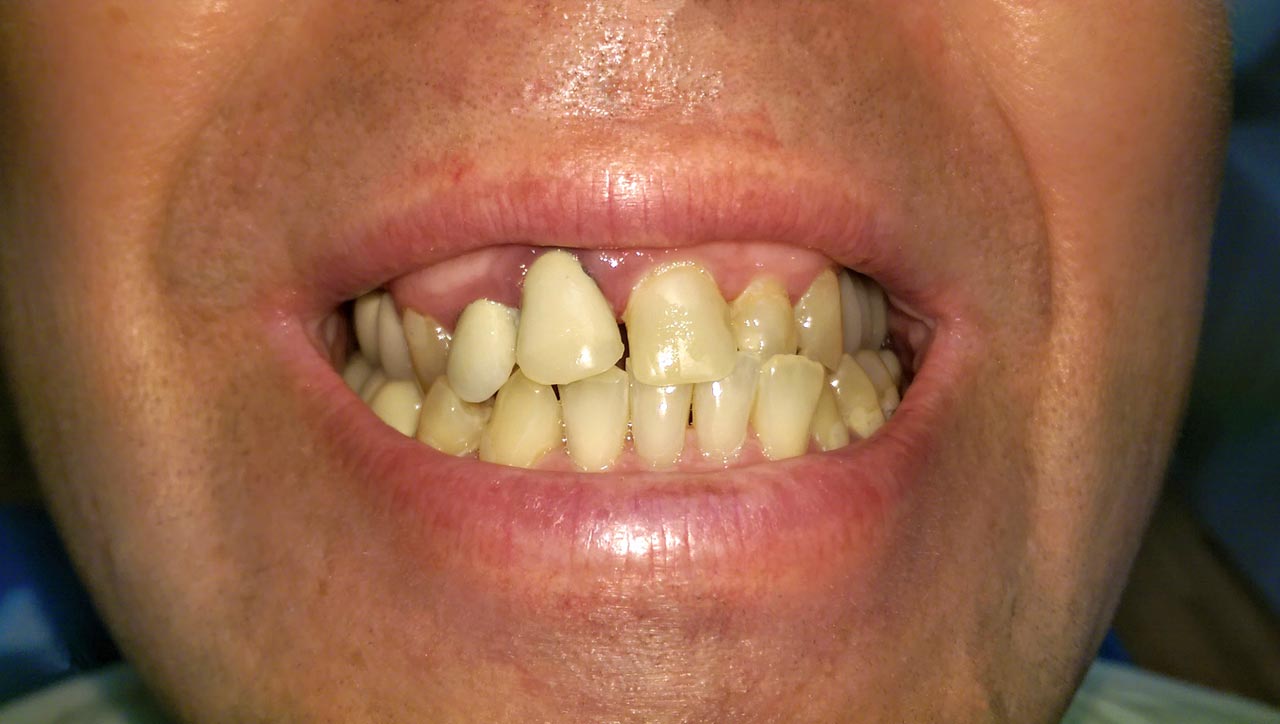

Elhanyagolt fogsor cseréje 2 nap alatt

2 nap alatt varázsoltuk ezt a szép esztétikus alsó, felső körhídat implantátumokkal megtámasztva a korábban elhanyagolt szájba. Az 1. nap 26 fogat távolítottunk el, mert annyira rossz állapotban voltak, és rögtön azonnal terhelhető IHDE svájci implantátumokat raktunk be, fentre 8, lentre 6 darabot. A sebeket összevarrtuk és intraorális szkennerrel digitális lenyomatot vettünk. 2 nap múlva pedig beragasztottuk a kész PMMA műanyag körhidakat. Dr. Kelemen Péter és a Symbion Fogtechnika munkája.